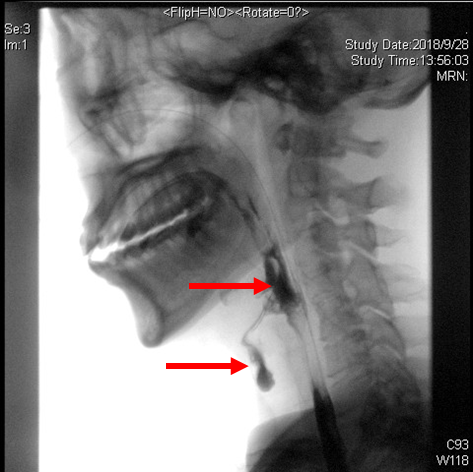

(1)电视荧光吞咽造影检查(Videofluroscopic Swallowing Study, VFSS):如图所示可看出,食管上有液体堆积,难以下咽(环咽肌开放不足);存在明显的误吸(液体流到声门下);动态视频观察到会厌折返欠佳。